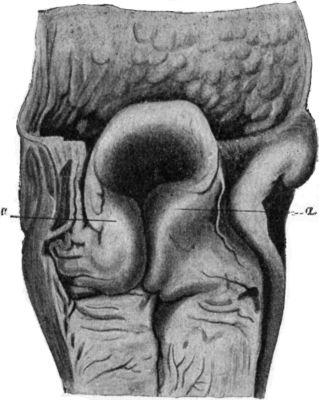

129.Innominate Bone and Upper End of Femur from a case of Congenital Dislocation of Hip250

130.Congenital Dislocation of Left Hip in a Girl251